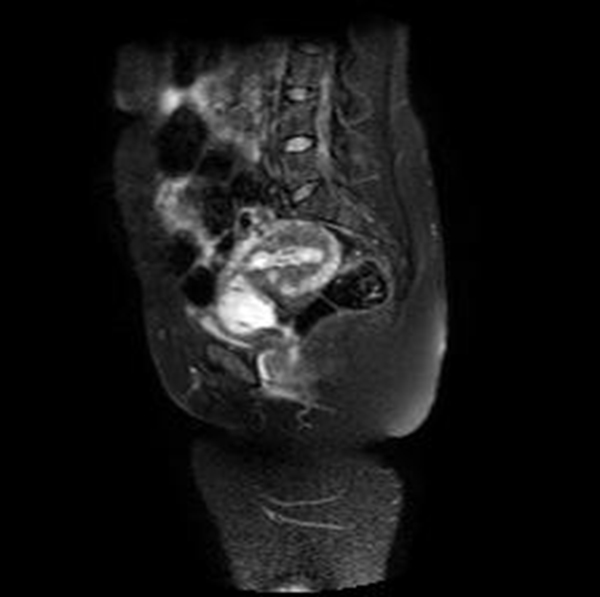

Se realizó una RNM (Philips 1.5 Tesla) que permitió confirmar el diagnóstico de EEC (figuras 5 a 8).

Figura 5A Imágenes sagitales de RMN potenciadas en T2 (TR: 1540 TE: 70) y T2 de disparo único (TR: 709 TE: 315) que muestran el saco gestacional hiperintenso localizado en el canal cervical y con tejido fetoplacentario en su interior, más evidente en la imagen B. Nótese que los orificios cervicales interno y externo se encuentran cerrados

Figura 5B Imágenes sagitales de RMN potenciadas en T2 (TR: 1540 TE: 70) y T2 de disparo único (TR: 709 TE: 315) que muestran el saco gestacional hiperintenso localizado en el canal cervical y con tejido fetoplacentario en su interior, más evidente en la imagen B. Nótese que los orificios cervicales interno y externo se encuentran cerrados